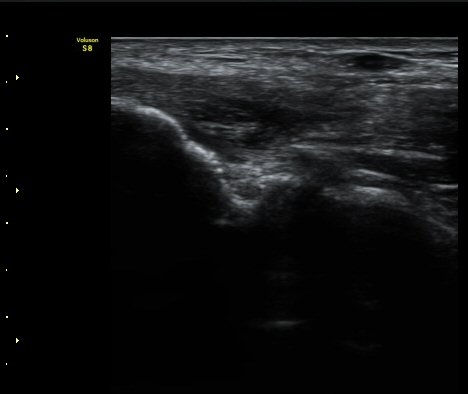

ÃÊÀ½ÆÄ °Ë»ç

³»»ó°ú¿¡¼­ ¼Õ¸ñ±¼°î°Ç Á¾´Ü¸é°Ë»ç»ó ³»¤µ¾Æ°ú ÇÇÁú°ñÀÇ ºÒ±ÔÄ¢º¯È­¿Í ÈûÁÙ³» ¿¬°á¼º

¼Ò½Ç ¹× Àü¹ÝÀûÀÎ Àú¿¡ÄÚ ºÎÁ¾ÀÌ °üÂûµÈ´Ù(±×¸² 1, 2, 3). ±¼°î°Ç ÀϺδ Á¤»óÀûÀÎ °í¿¡ÄÚ

¼¶À¯ ¾ç»óÀ¸·Î °üÂûµÈ´Ù(±×¸² 4). ÈûÁ٠Ⱦ´Ü¸é °Ë»ç¿¡¼­µµ °Ç³» ¿¬°á¼º ¼Ò½Ç°ú Àú¿¡ÄÚ

º¯È­°¡ °üÂûµÈ´Ù(±×¸² 5).  ÃÊÀ½ÆÄÀ¯µµÇÏ ÁÖ»ç ½Ã ÁÖ»ç¾×ÀÌ °Ç³»¿¡¼­ ÀÚÀ¯·Ó°Ô ÆÛÁ®¼­

°ÇÀÇ ½ÉÇÑ ÆÄ¿­À» º¸¿©ÁØ´Ù(÷ºÎ ÆÄÀÏ µ¿¿µ»ó 1).